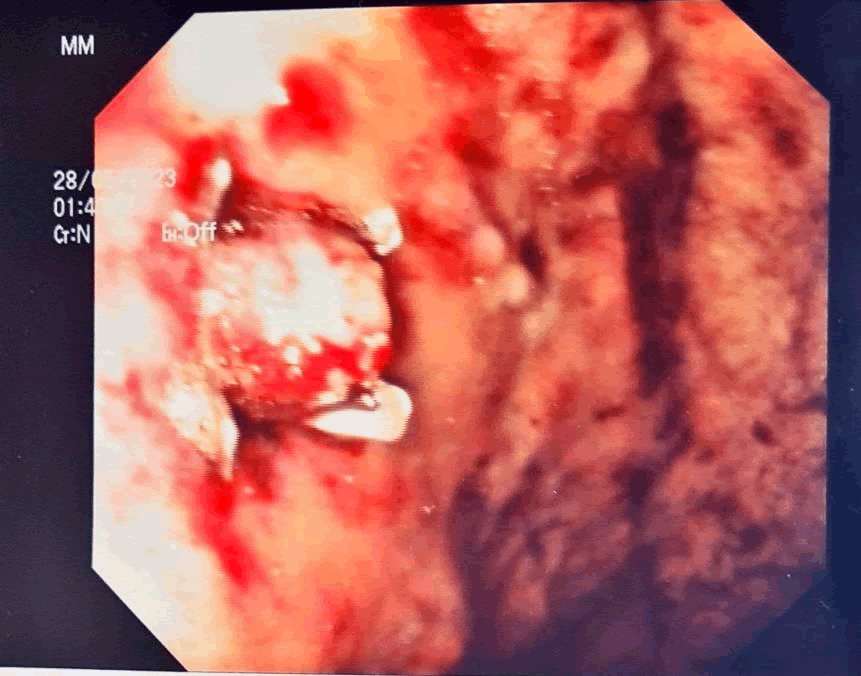

A 30+0 weeks of gestational age male newborn was delivered after 2 minutes, with Apgar score of 1-5-7 at 1-5-10 minutes. In the meantime, EGD was performed. After multiple washings and aspiration of the gastric hematic content, despite changes of the patient’s position, the bleeding site was not identified. A CT-angiography was then performed; however, no active bleeding was evidenced. Straight afterwards, a second EGD was performed and, after removal of blood clots, a bleeding DL was eventually identified on the anterior wall of gastric fundus (Figure 2). Epinephrine was injected, and over-the-scope endoclip was placed obtaining hemostasis (Figure 3).

XXXXXX

Figure 3. GI endoscopy showing treated lesion and obtained hemostasis.